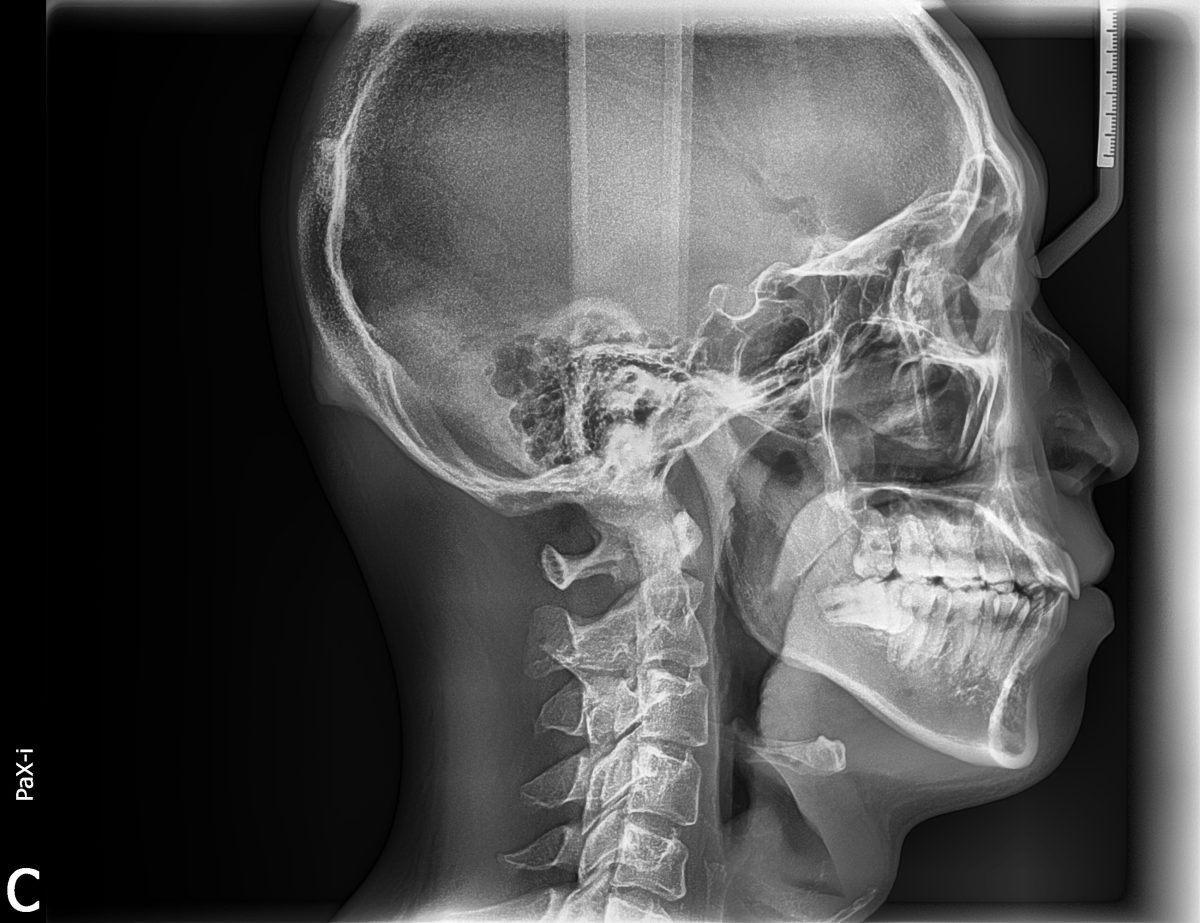

今回紹介する症例は口元が出ていて口が閉じにくいことで来院されました。上顎小臼歯抜歯による治療を選択しました。

上下顎ともに叢生(歯並びの乱れ)がほとんどないため、抜歯スペースを最大限利用して口元を下げていく予定です

治療半ばから治療効率を上げるために上顎右側にアンカースクリューを埋入しました。

動的治療期間は2年6カ月でした。

治療後は口元がかなり下がったため口が楽に閉じれるようになったととても喜ばれました。

今回紹介する症例は口元が出ていて口が閉じにくいことで来院されました。上顎小臼歯抜歯による治療を選択しました。

上下顎ともに叢生(歯並びの乱れ)がほとんどないため、抜歯スペースを最大限利用して口元を下げていく予定です

治療半ばから治療効率を上げるために上顎右側にアンカースクリューを埋入しました。

動的治療期間は2年6カ月でした。

治療後は口元がかなり下がったため口が楽に閉じれるようになったととても喜ばれました。